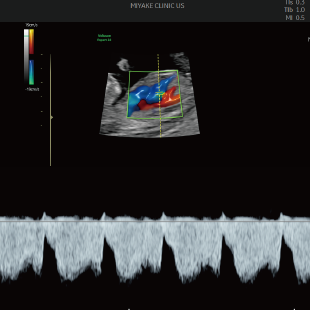

初期スクリーニングでは、首の後ろのむくみ(Nuchal translucency: NT)や鼻の骨、心臓まわりの血流などを確認し、胎児の体の特徴や発育の様子を丁寧に観察します。 これらの所見は、染色体数の変化と関連することがある特徴として知られており、21トリソミー/18トリソミー/13トリソミーなどの染色体変化の可能性を評価する指標となります。(本検査のみで確定診断はできません) また観察可能な範囲において脳や脊椎、心臓、消化管、手足などに大きな形態の変化がないかについても確認を行います。

胎児ドックの様子_初期 胎児ドックの様子_初期 胎児ドックの様子_初期 胎児ドックの様子_初期 胎児ドックの様子_初期 胎児ドックの様子_初期 胎児ドックの様子_初期 胎児ドックの様子_初期